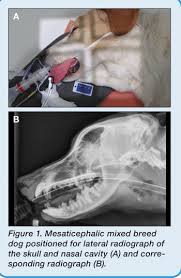

The Fluid Dynamics Of Canine Olfaction Unique Nasal Airflow Patterns As An Explanation Of Macrosmia Journal Of The Royal Society Interface from royalsocietypublishing.org They are separated by a bony plate or septum until they end at the nasopharynx. The frontal sinus has 3 chambers which drain separately into the nasal cavity. The nasal cavities house the turbinate bones and paranasal sinuses. The nasal cavity is occupied to a large extent by nasal conchae. It makes up the upper respiratory system along with the paranasal sinuses, oral cavity, pharynx, and larynx 2, and is the. Radiography of specific areas requires close attention to small details of anatomy. There are two passages, one on each side of the nose. Images are available in 3 different planes (transverse, sagittal and dorsal), with two kind of contrast (bone and soft tissues).